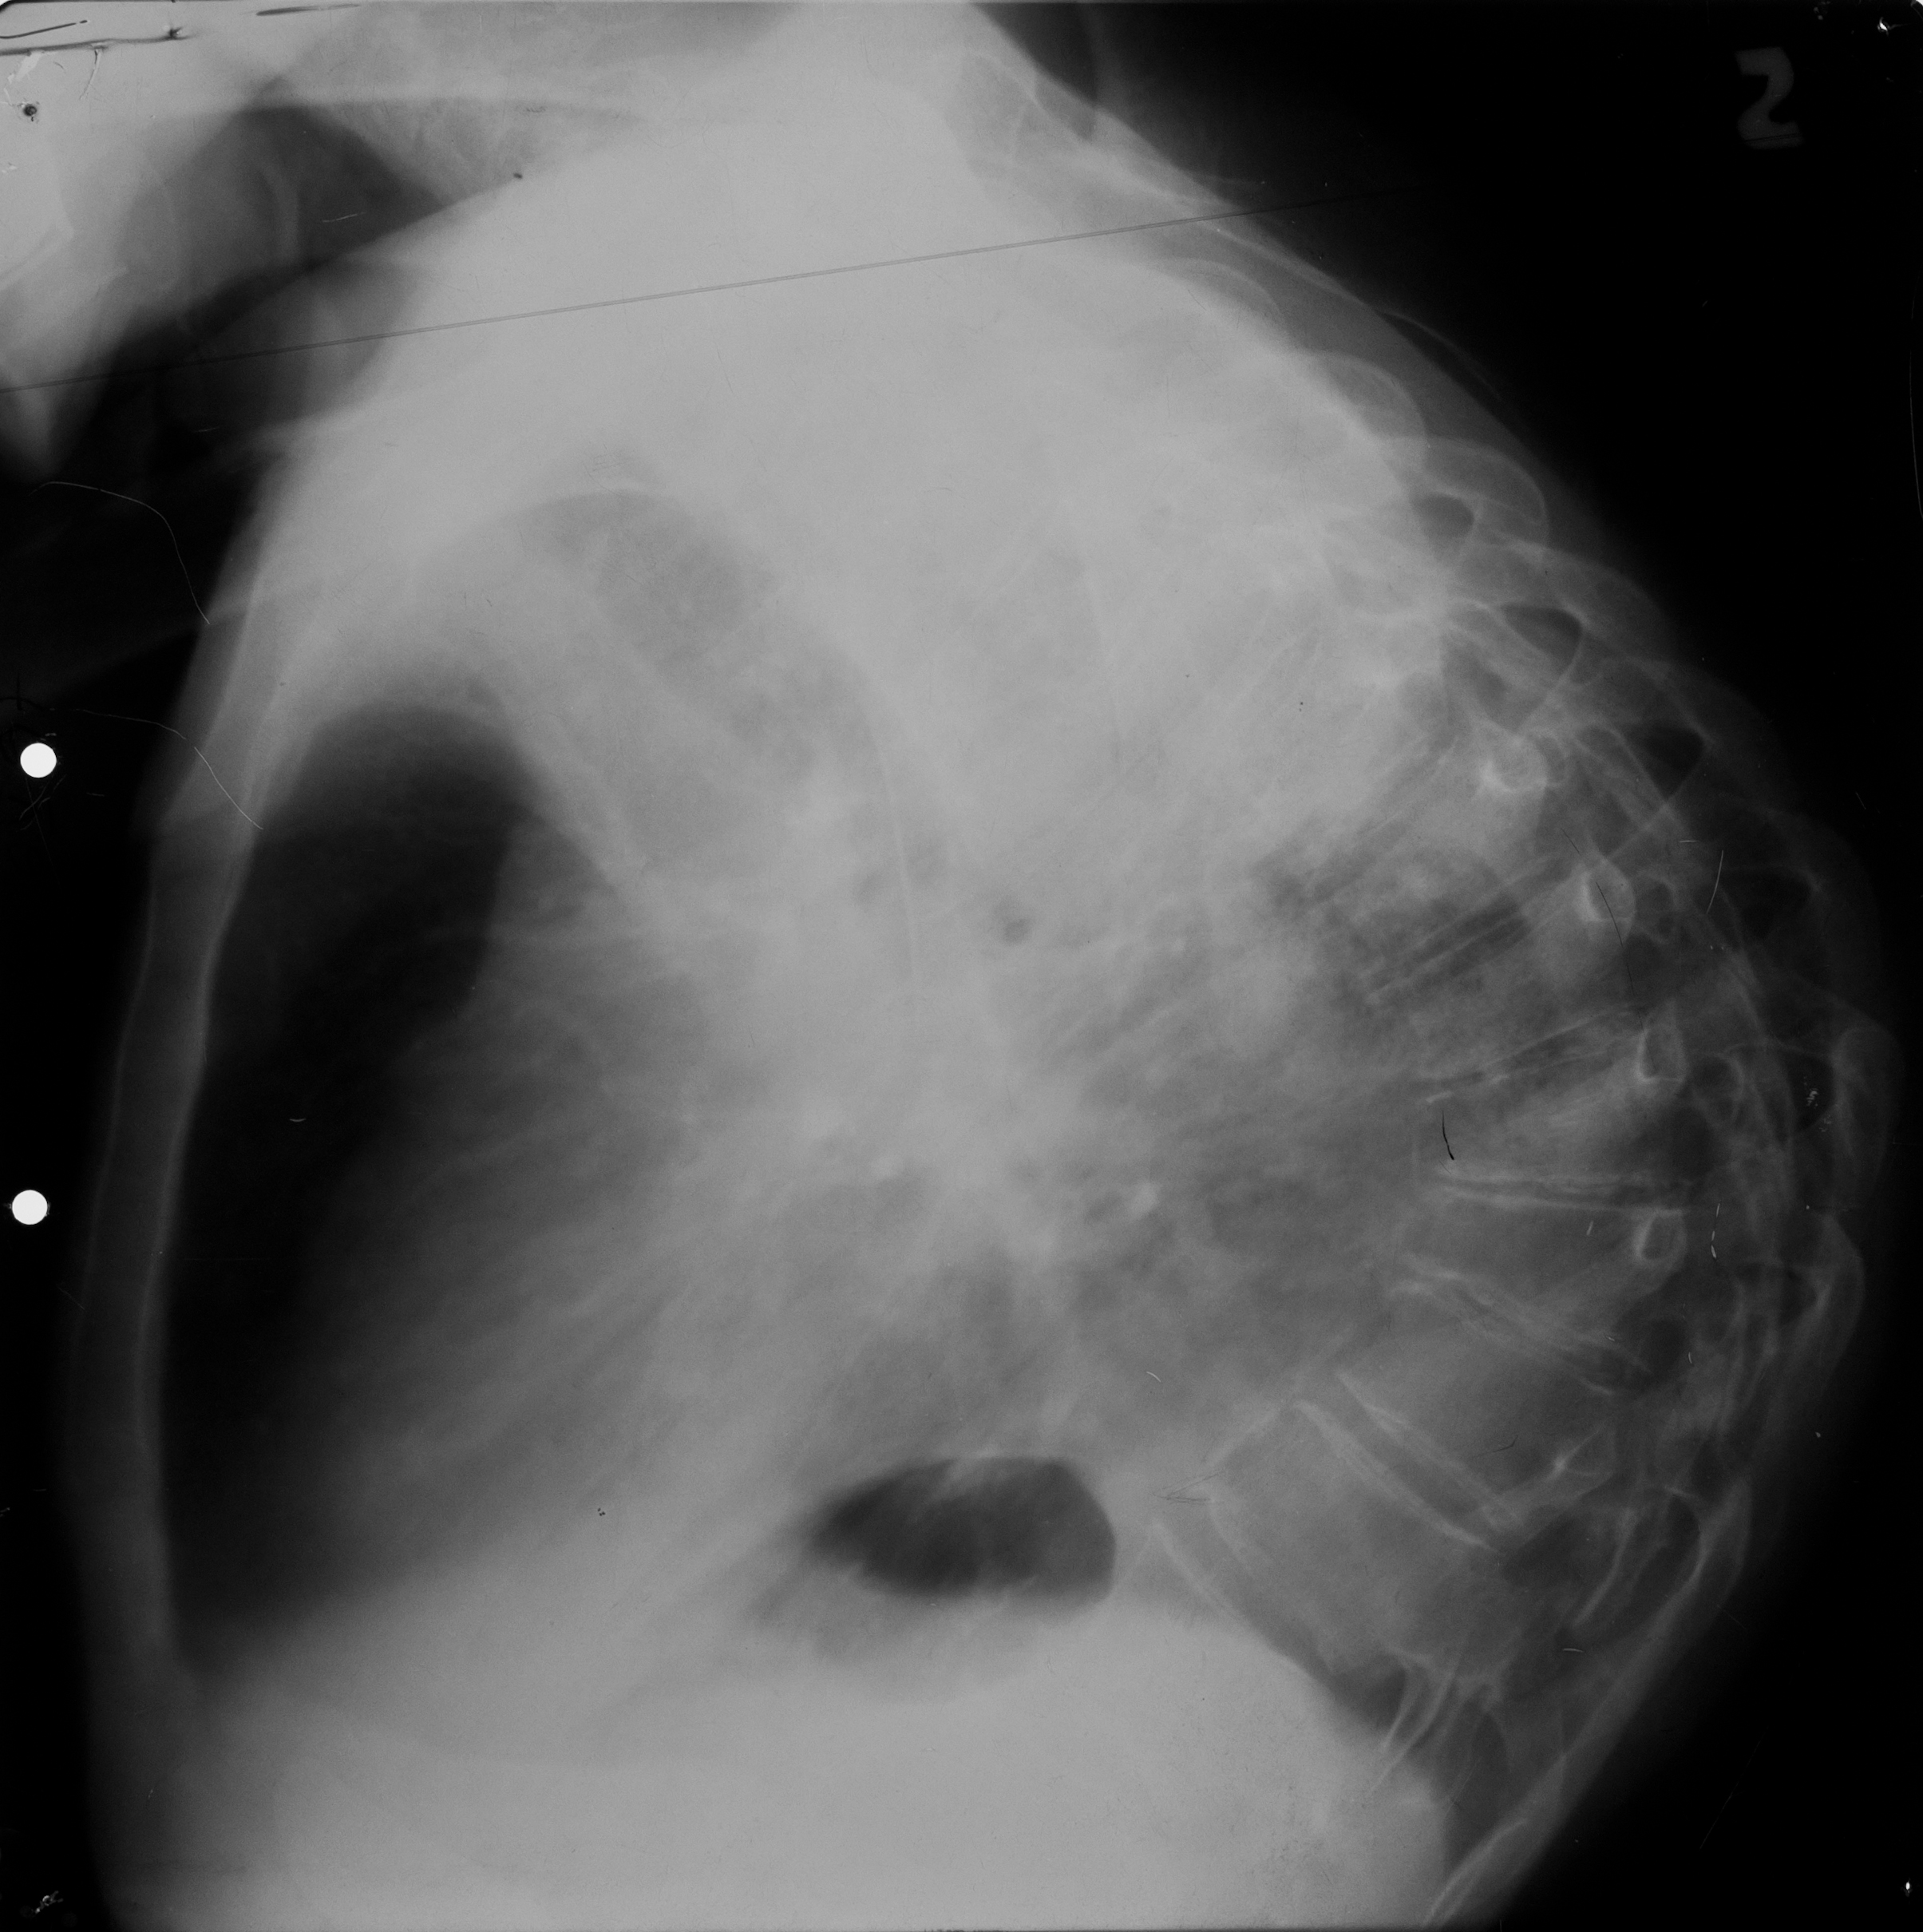

Rx toraco-mediastino-pleuro-pulmonar,de profil – opacitate

CHIST SUPRAINFECTAT VĂZUT DIN PROFIL (radiografie de profil)

Imagine hidroaerică,mixtă